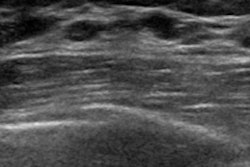

Outpatient radiology group SimonMed Imaging and computer-aided detection (CAD) software developer QView Medical have entered into a partnership to provide artificial intelligence (AI) services for 3D breast ultrasound exams.

The two firms will incorporate breast ultrasound AI into QView Medical's AI/QVCAD system to help radiologists improve their breast cancer detection rates and reduce callbacks.